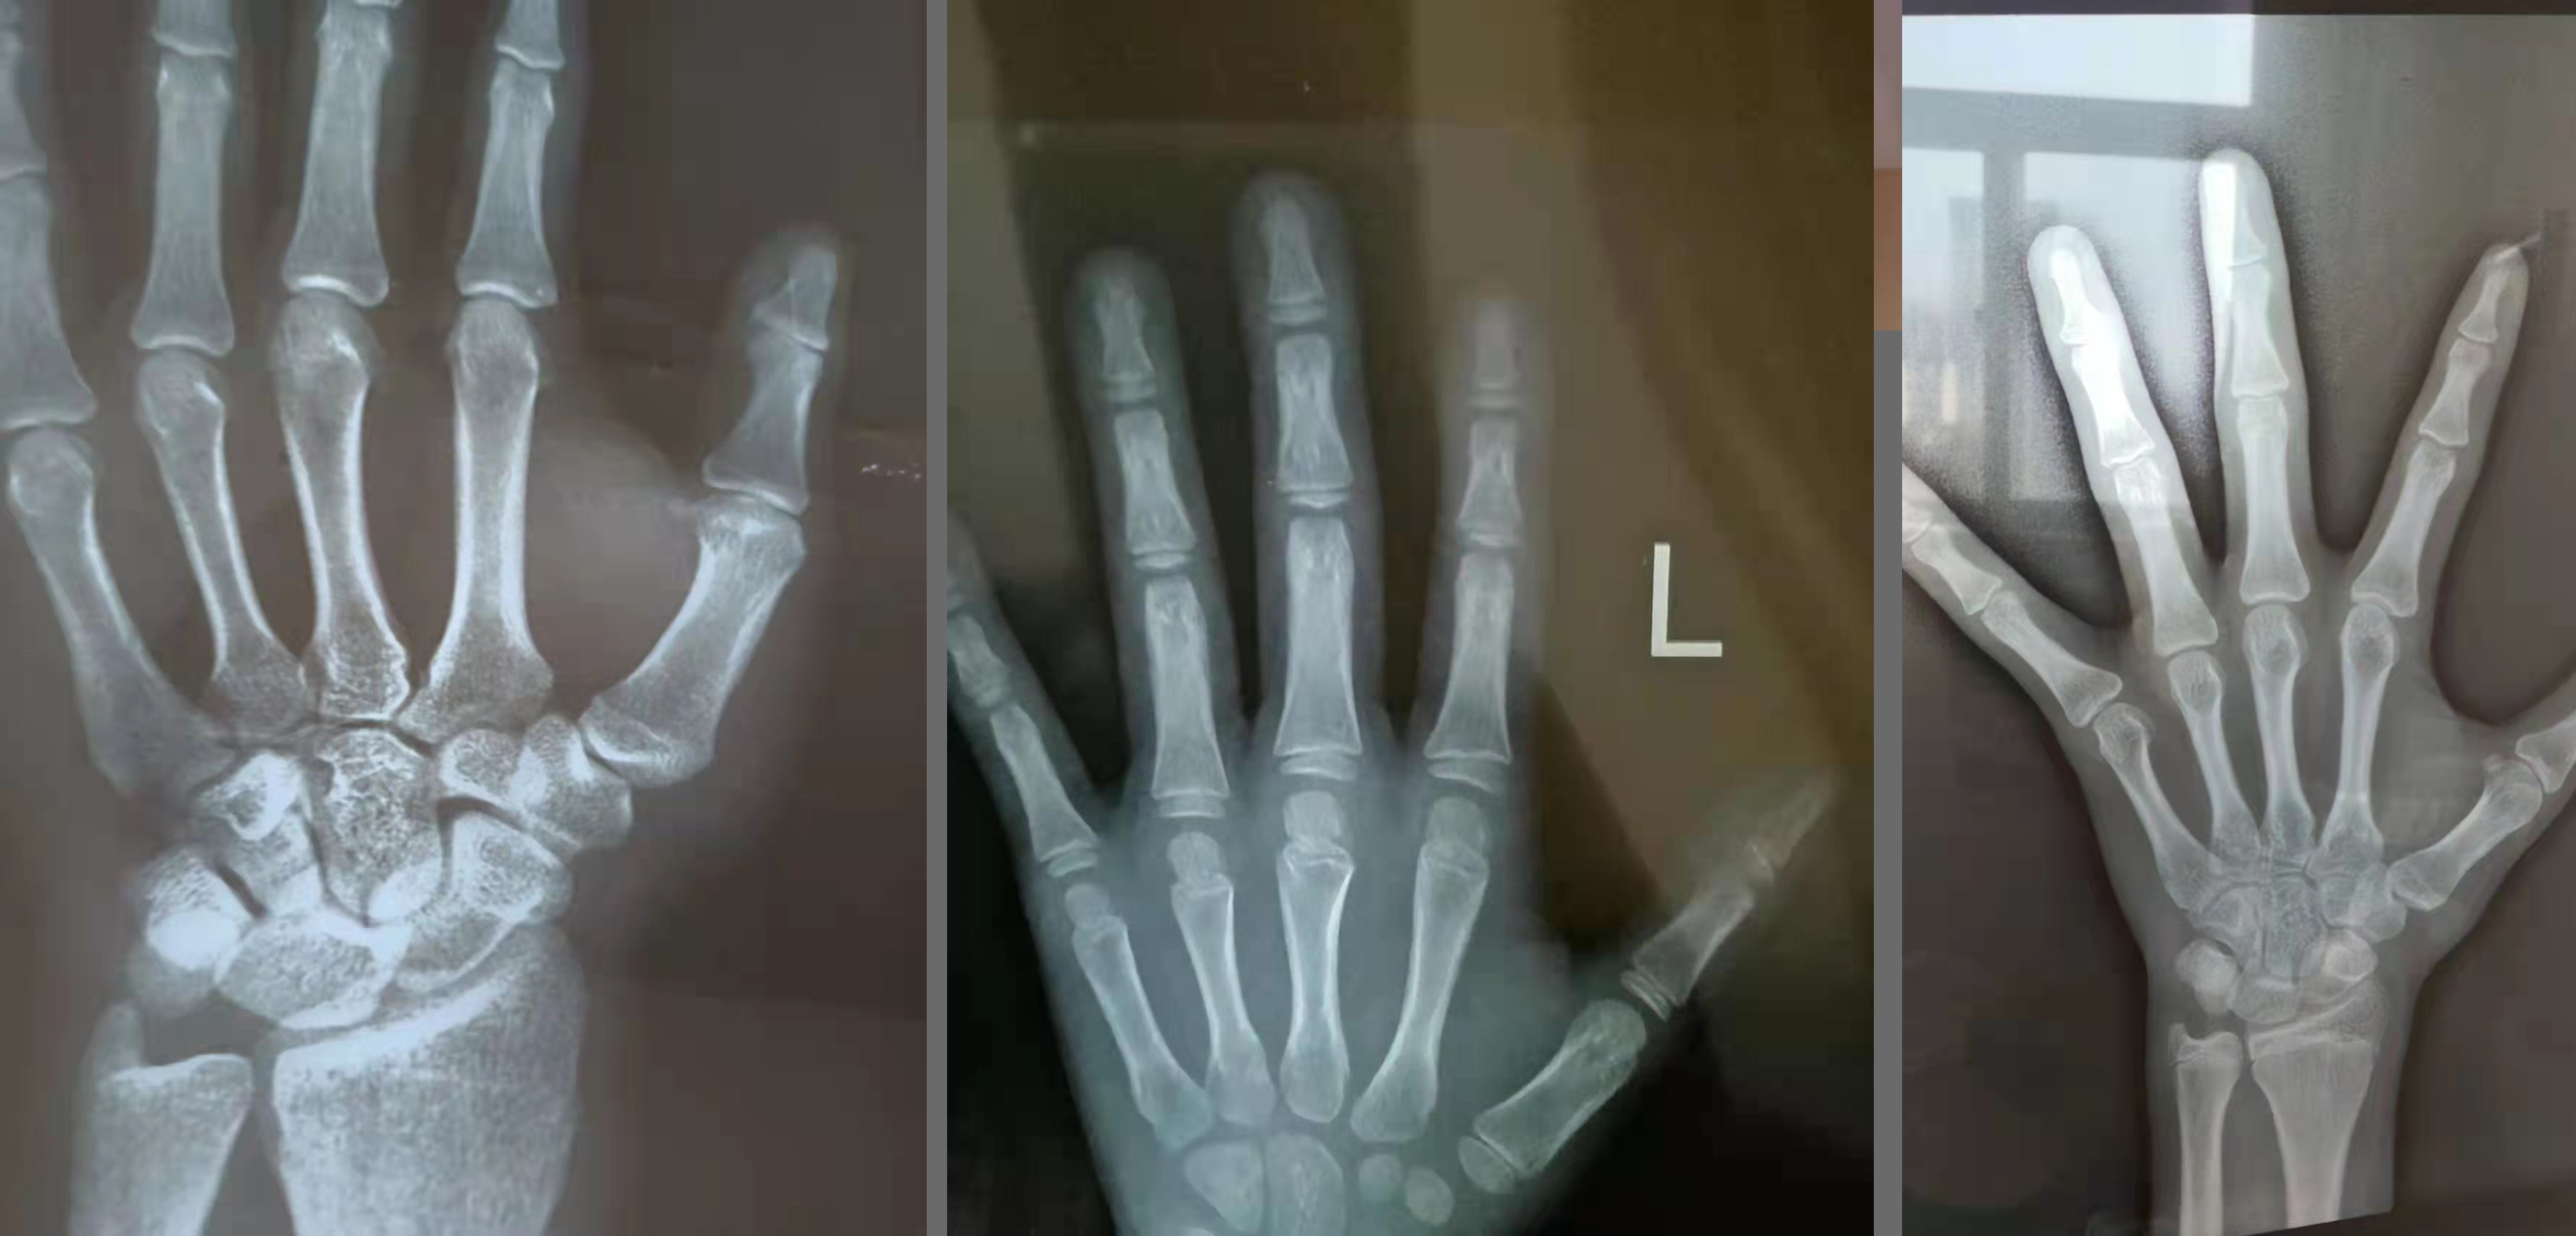

手势不标准的

拍骨龄片时五指自然分开,掌心向下

没拍全的

骨龄片要拍全整个手掌

拍反的

大拇指朝右才是正确的

骨龄片拍成右手的

一般拍左手正位x光片